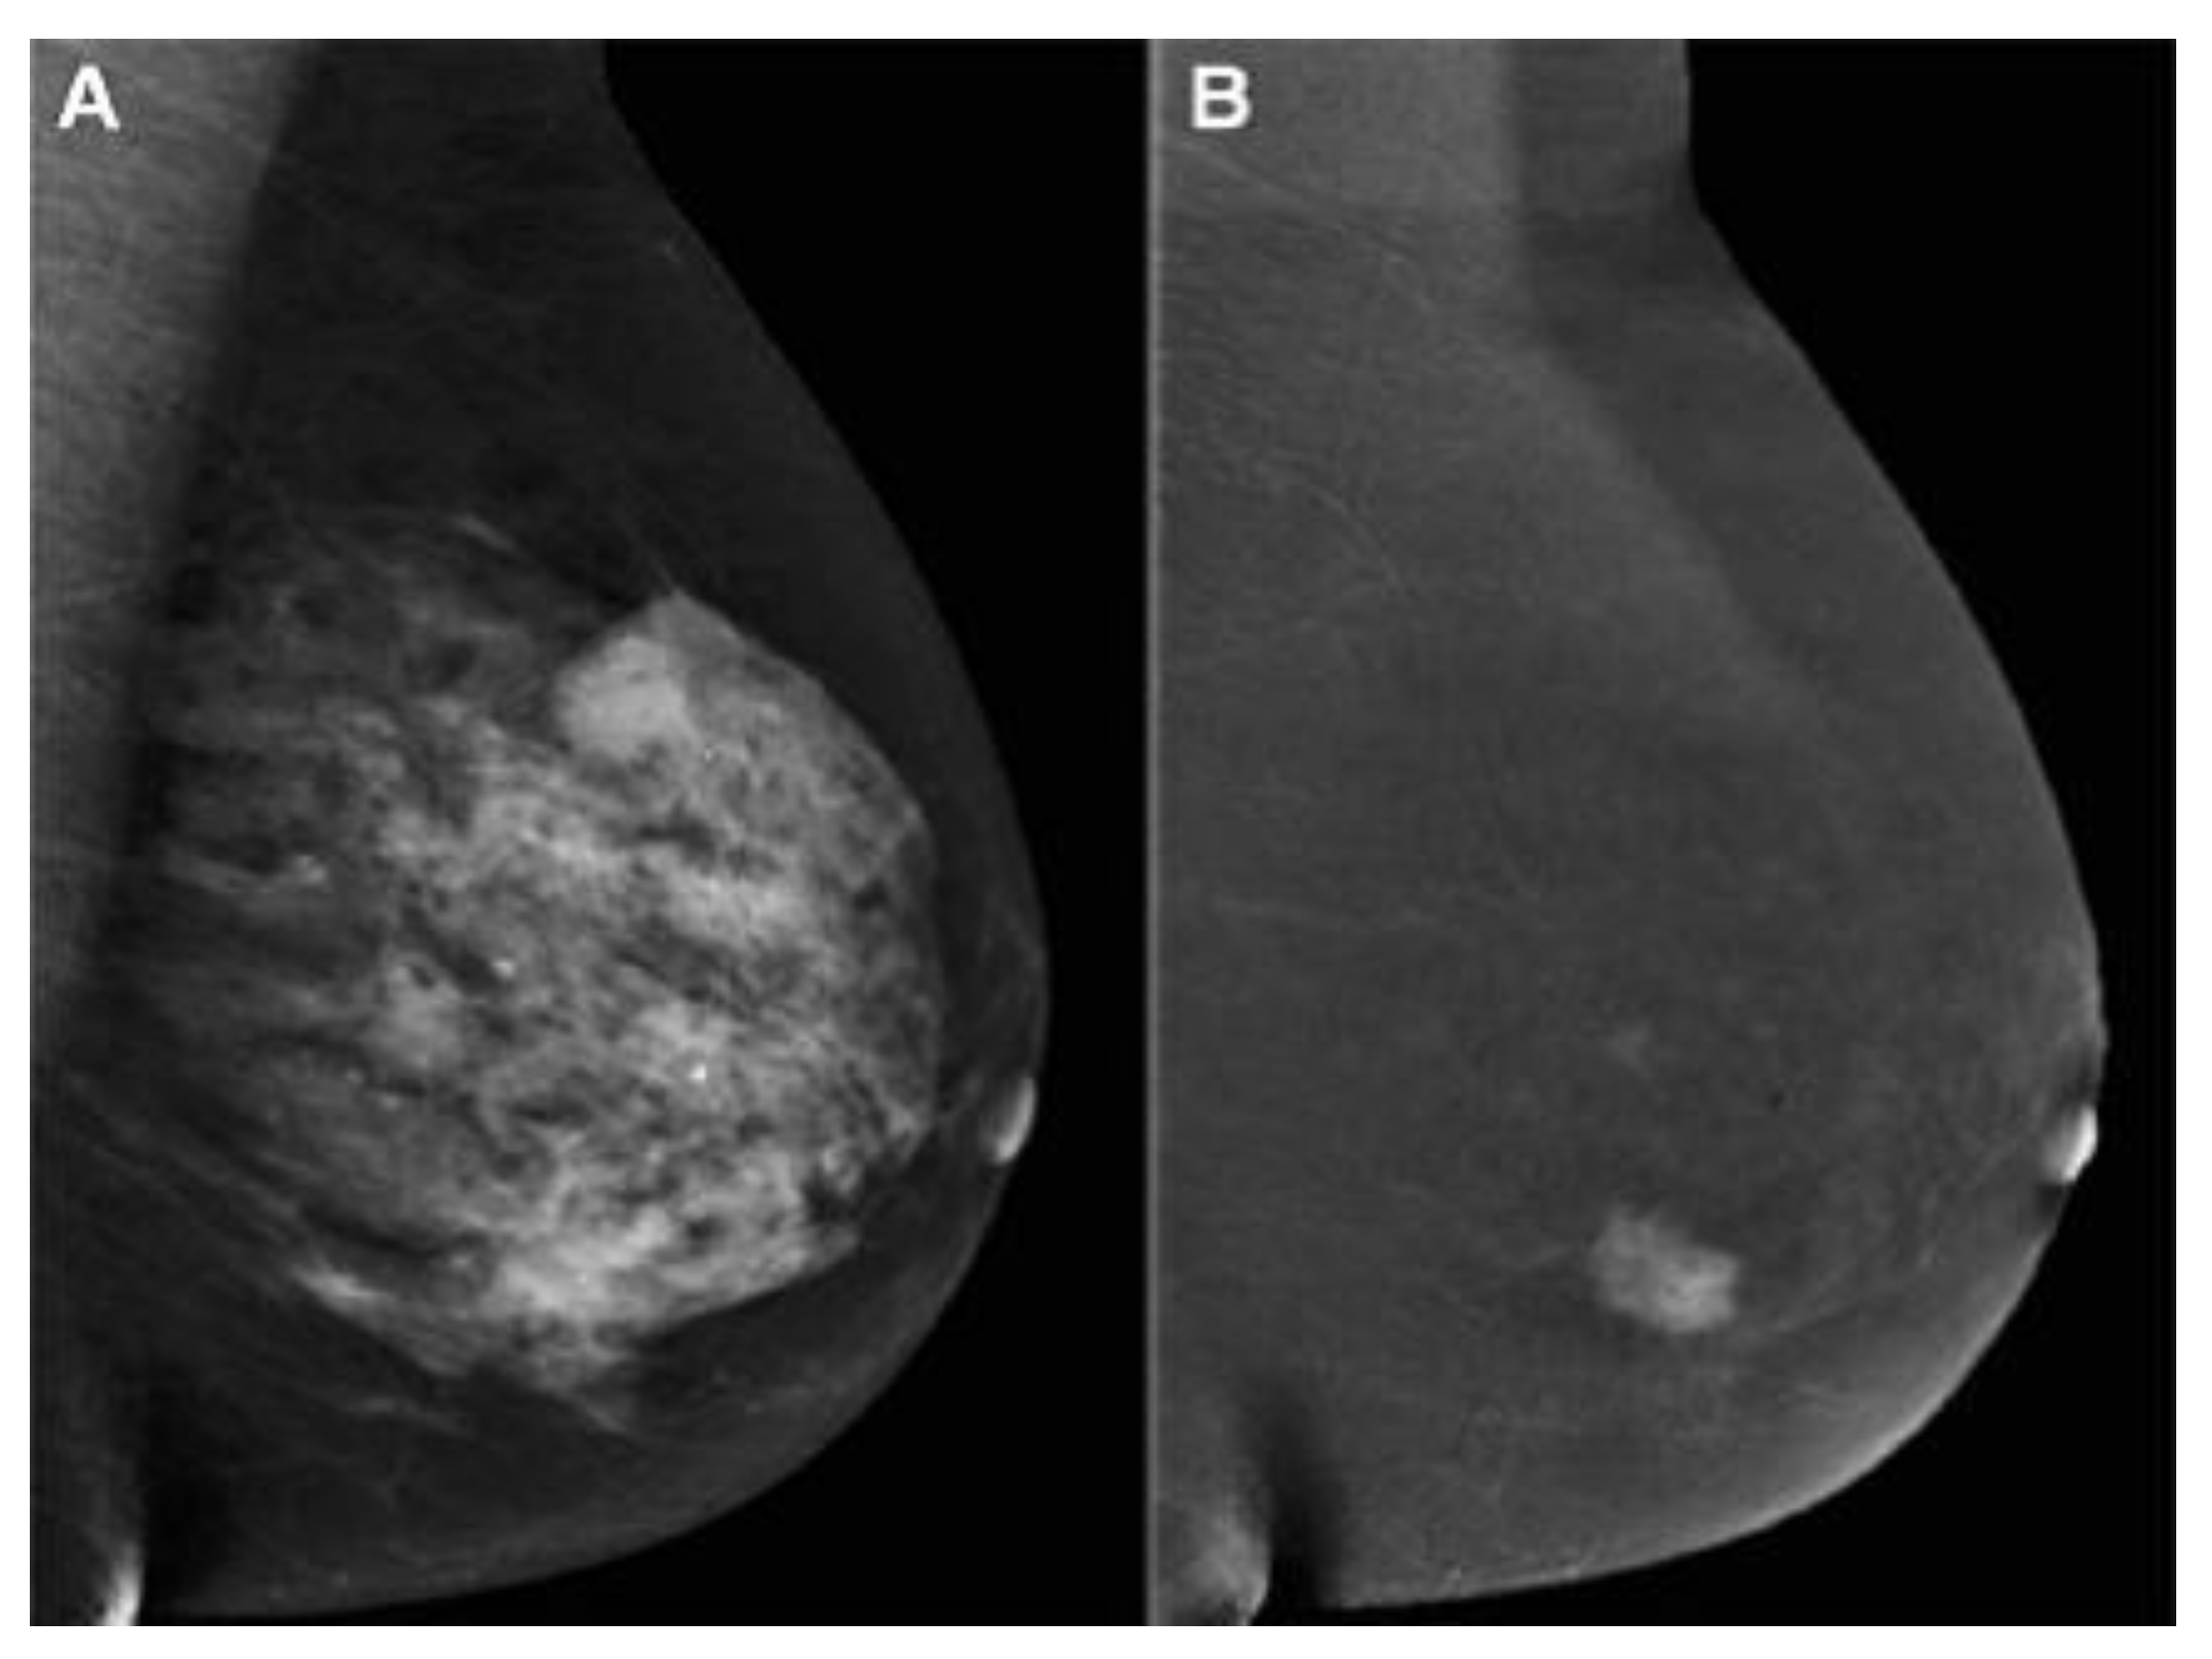

2.3. Contrast-Enhanced Mammography (CEM)

- Ghaderi, K.F.; Phillips, J.; Perry, H.; Lotfi, P.; Mehta, T.S. Contrast-enhanced mammography: Current applications and future directions. Radiographics 2019, 39, 1907–1920. [Google Scholar] [CrossRef] [PubMed]

- Mori, M.; Akashi-Tanaka, S.; Suzuki, S.; Daniels, M.I.; Watanabe, C.; Hirose, M.; Nakamura, S. Diagnostic accuracy of contrast-enhanced spectral mammography in comparison to conventional full-field digital mammography in a population of women with dense breasts. Breast Cancer 2017, 24, 104–110. [Google Scholar] [CrossRef]

- Kim, G.; Phillips, J.; Cole, E.; Brook, A.; Mehta, T.; Slanetz, P.; Fishman, M.D.C.; Karimova, E.; Mehta, R.; Lotfi, P.; et al. Comparison of Contrast-Enhanced Mammography With Conventional Digital Mammography in Breast Cancer Screening: A Pilot Study. J. Am. Coll. Radiol. 2019, 16, 1456–1463. [Google Scholar] [CrossRef]

- Sorin, V.; Yagil, Y.; Yosepovich, A.; Shalmon, A.; Gotlieb, M.; Neiman, O.H.; Sklair-Levy, M. Contrast-enhanced spectral mammography in women with intermediate breast cancer risk and dense breasts. AJR Am. J. Roentgenol. 2018, 211, W267–W274. [Google Scholar] [CrossRef] [PubMed]

- Sudhir, R.; Sannapareddy, K.; Potlapalli, A.; Krishnamurthy, P.B.; Buddha, S.; Koppula, V. Diagnostic accuracy of contrast-enhanced digital mammography in breast cancer detection in comparison to tomosynthesis, synthetic 2D mammography and tomosynthesis combined with ultrasound in women with dense breast. Br. J. Radiol. 2021, 94, 20201046. [Google Scholar] [CrossRef] [PubMed]

- Li, L.; Roth, R.; Germaine, P.; Ren, S.; Lee, M.; Hunter, K.; Tinney, E.; Liao, L. Contrast-enhanced spectral mammography (CESM) versus breast magnetic resonance imaging (MRI): A retrospective comparison in 66 breast lesions. Diagn. Interv. Imaging 2017, 98, 113–123. [Google Scholar] [CrossRef] [PubMed]

- Phillips, J.; Miller, M.M.; Mehta, T.S.; Fein-Zachary, V.; Nathanson, A.; Hori, W.; Monahan-Earley, R.; Slanetz, P.J. Contrast-enhanced spectral mammography (CESM) versus MRI in the high-risk screening setting: Patient preferences and attitudes. Clin. Imaging 2017, 42, 193–197. [Google Scholar] [CrossRef] [PubMed]

- Bozzini, A.; Nicosia, L.; Pruneri, G.; Maisonneuve, P.; Meneghetti, L.; Renne, G.; Vingiani, A.; Cassano, E.; Mastropasqua, M.G. Clinical performance of contrast-enhanced spectral mammography in pre-surgical evaluation of breast malignant lesions in dense breasts: A single center study. Breast Cancer Res. Treat. 2020, 184, 723–731. [Google Scholar] [CrossRef] [PubMed]

- Chou, C.-P.; Lewin, J.M.; Chiang, C.-L.; Hung, B.-H.; Yang, T.-L.; Huang, J.-S.; Liao, J.-B.; Pan, H.-B. Clinical evaluation of contrast-enhanced digital mammography and contrast enhanced tomosynthesis—Comparison to contrast-enhanced breast MRI. Eur. J. Radiol. 2015, 84, 2501–2508. [Google Scholar] [CrossRef]

- Huang, J.-S.; Pan, H.-B.; Yang, T.-L.; Hung, B.-H.; Chiang, C.-L.; Tsai, M.-Y.; Chou, C.-P. Kinetic patterns of benign and malignant breast lesions on contrast enhanced digital mammogram. PLoS ONE 2020, 15, e0239271. [Google Scholar] [CrossRef]